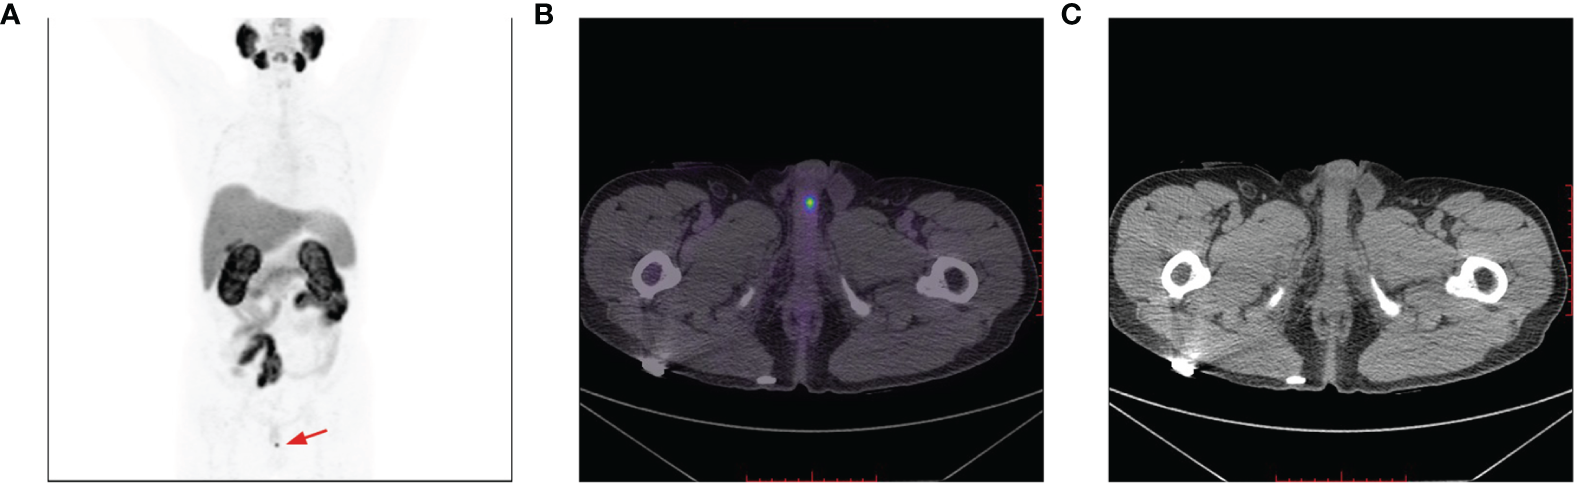

Figure 4

A 18F-PSMA-1007 PET/CT avid solitary penile lesion with a SUVmax of 6.4 (A, B); no morphological abnormalities of the penis detected on CT imaging (C).